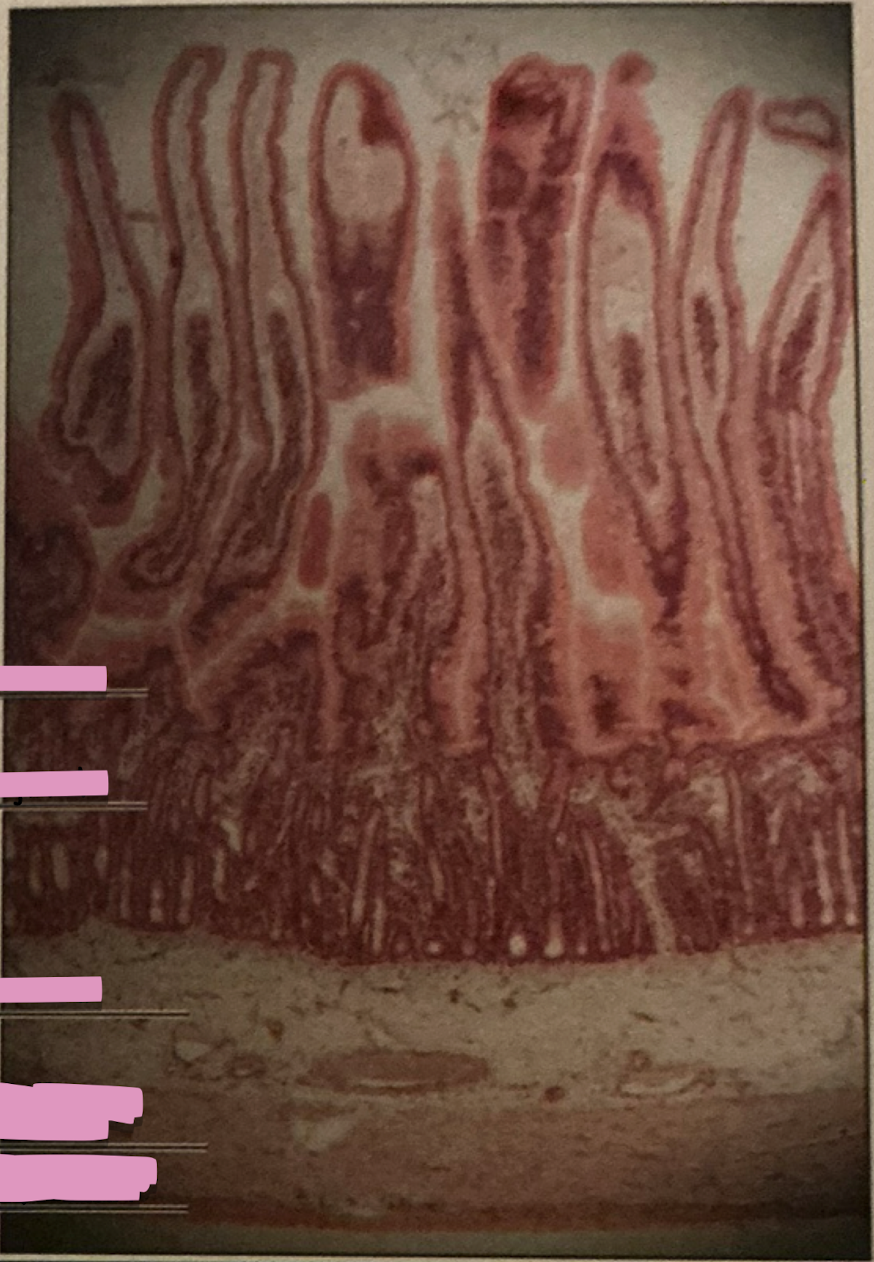

duodenum

jejunum

iluem

duodenum

duodenum

________ receives chyme when stomach empties; exocrine release site for gallbladder & pancreatic secretions

intestinal glands

secrete mix of sucrase, maltase, & peptidases + definsins & enzymes

brunner’s glands

produce mucus-rich alkaline secretion to protect from acidic content, lubricate walls, & enable absorption

goblet cells

single-celled exocrine glands secrete mucus

jejunum

ileum

jejunum

mid segment of SI, function in absorption

ileum

last part of SI, absorption of vitamin B12 bound to intrinsic factor

peyer’s patches

lymph tissue in submucosa - end of ileum

colon

large intestines

where formation of feces by absorption of water occurs